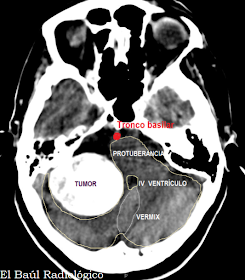

FIGURA 6-a) Meningioma calcificado que producía hidrocefalia. TC sin contraste endovenoso.